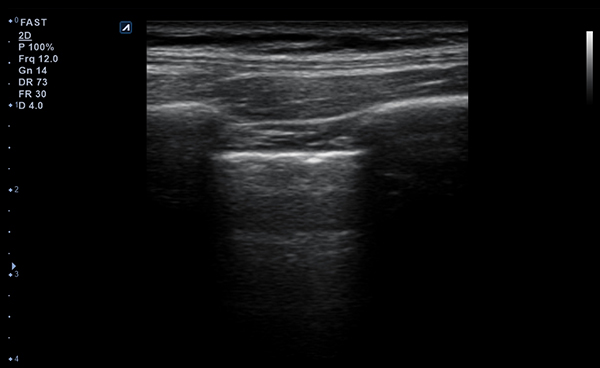

- Frequency3-12 MHz

- Dimension (height/width/depth)25.2 / 62.5/ 150mm

- Weight 175g

- Field of view 38.4mm

- Max depth10 cm

- Imaging modesB-mode, CF, M, PW, PD

- DisplayMicrosoft Surface

- Battery300 min